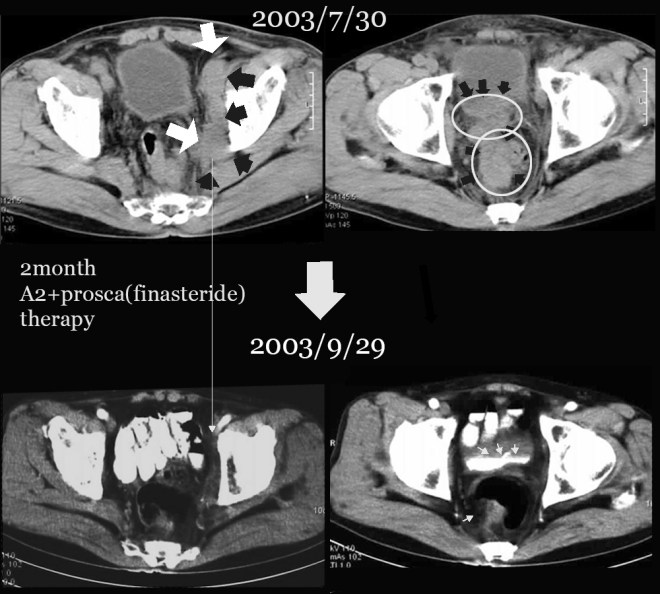

전립선암이 열어 보니 방광 대장을 다 침범하여서 거의 9cm 이상의 종양이 퍼져 있었고, 주변 ischial lymph node(골반 주위의 림프절)의 다발성전이가 있었던 분이다. 이후 본원에 와서 양방에서는 사용치 않는 양성 전립선비대를 억제하는 프로스카와 본원의 한방요법을 결합하여 전립선암이 거의 없어진 상태로  3년 이상을 정상생활을 하였고 그 후 술 담배를 다시 하기 시작하고 일년만에 다발성 폐전이가 되어서 폐렴합병증으로 사망한 사례이다. 자료를  2000 년도의 자료라 찾기가 어려워서 나중에 더 보충 자료를 넣어 보려고 하지만 본고에서는  2007 년도 본인이 삼성의료원의 산부인과 배덕수 과장 소개로 한의학의 암치료에 대한 강의를 초청받아서 갔을 때 자료를 가지고 이 환자의 사례를 설명해 보겠다.

나이는 74세로 당시 뼈전이와 골반벽전이 대장방광전이가 있어서 열었다 바로 닫아버리고  2달선고를 받고 나서 한방을 찾았다. 위에서 보듯이 경추에 전이가 있었고, 아래 사진과 같이 약 9cm 정도의 종양이 방광벽을 침범하여서 방광이 일그러져 보이고(하얀 소변이 찬 부분 아래쪽면) 대장도 밀려서 화살표에서 보는 작은 점이 남아 있는 대장의 크기로 대변을 거의 못 보다시피 가늘게 나왔다.

1-4.jpg

가족 중에 따님이 나와 교우가 있는 사이라, 또 병원에서 두달 남았다 하니 우리 병원에 찾아와서 치료를 시작하였다. 나는 당시 양방 선생님께 부탁하여서 양성 전립선비대에 사용하는  프로스카와 한약 A2로 명명 지어진 종합한방약물을 투여하였다.

1-5.jpg

위의 CT에서 보듯이 왼쪽 사진에 흰 화살표와 검은 화살표로 경계 지어지는 부분은 왼쪽 골반뼈에 접한 림프절인데 거의 10cm 이상을 육박하고 우측 사진에서는 위쪽은 방광벽, 아래로는 대장을 침범한 사진을 볼 수 있다. 워낙이 복부에 퍼져 있어서 바로 보고 닫았다고 한다.

이후 나의 방법대로 A2라는 약물과 프로스카를 병행하여서 두 달여를 치료하였다. 양방에서는 이 프로스카라는 약물은 양성 전립선비대에만 사용하는 약물로 암에는 효과가 없다고들 양방 선생님들은 이야기 하지만 내가 보는 견해는 그와 다르다.

1-6.jpg

이 환자는 두 달여의 치료에 좌측 사진에서 보듯이 왼쪽 골반벽의 종양이 모두 소실이 되어서 아래 사진에서 보이지 않고, 우측도 마찬가지로 이전 검은 화살표에서 보는 방광벽의 침범이 아래 사진에서는 정상 소변이 차서(조영제가 하얗게 보임) 면이 매끄럽게 다 없어지고, 아래 대장쪽도 다 소실이 된 상태이다.

1-7.jpg

이 환자는  이후  9 개월간의 사진을  이전 발표본을 그대로  수록해본다.